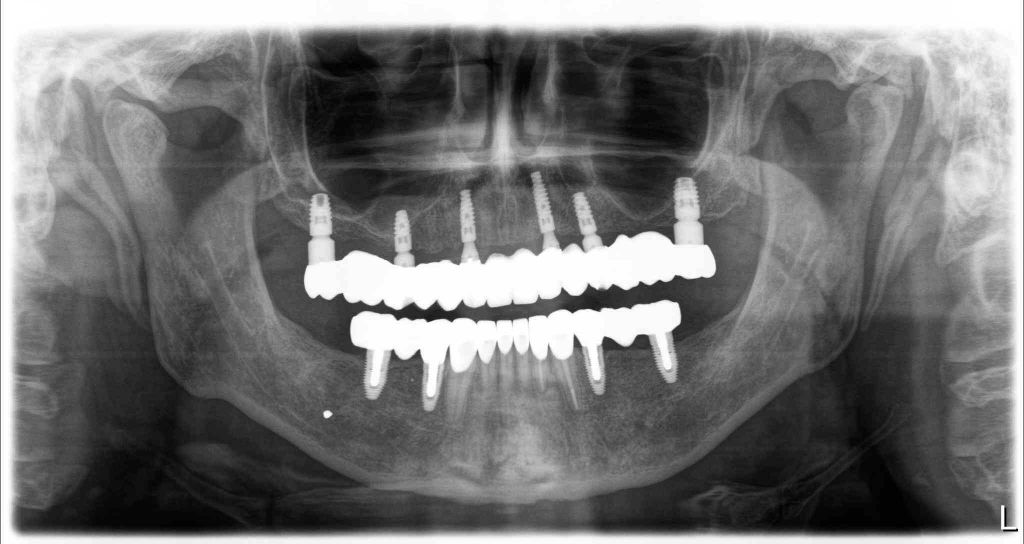

Zirconia bridge on Southern DC Implants